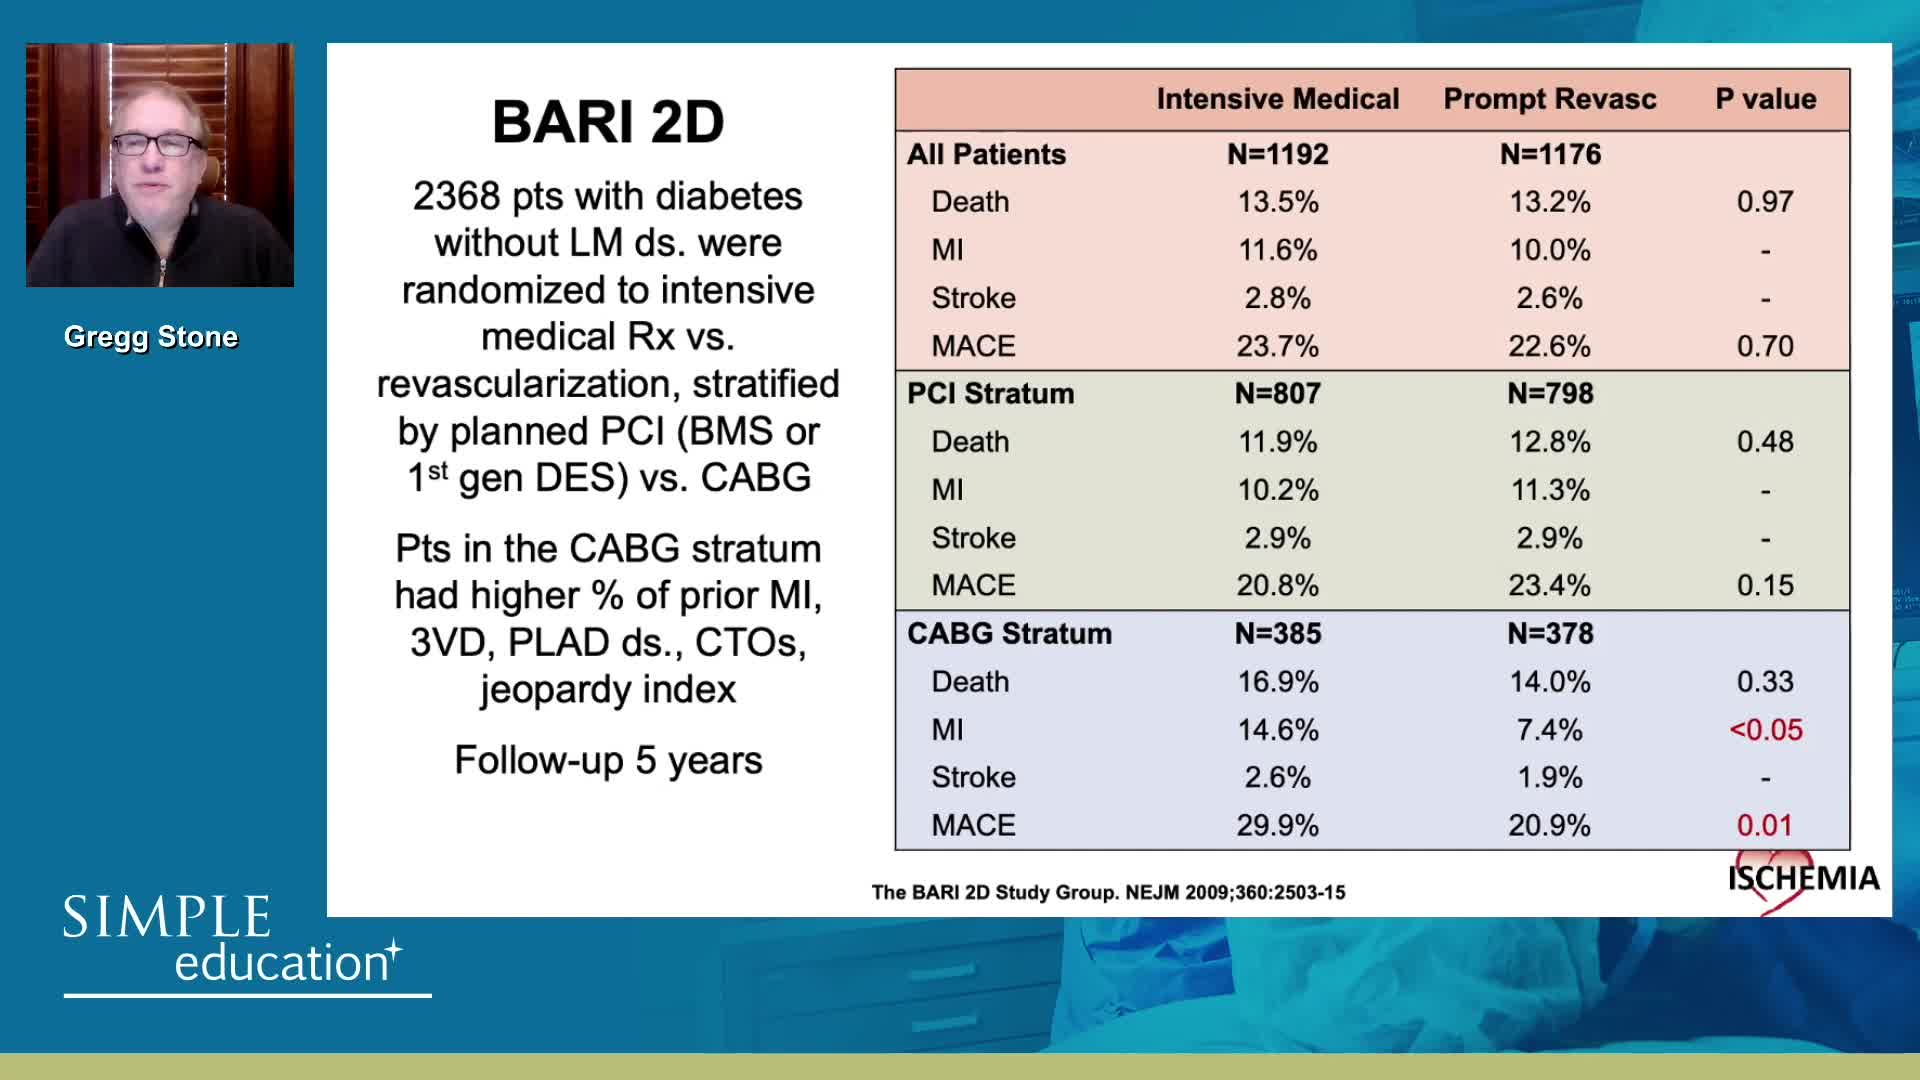

20 year overview of clinical trial data to support the use of coronary physiology in revascularisation decision-making

Revascularisation in stable angina: a contemporary perspective - Dr Rasha Al-Lamee